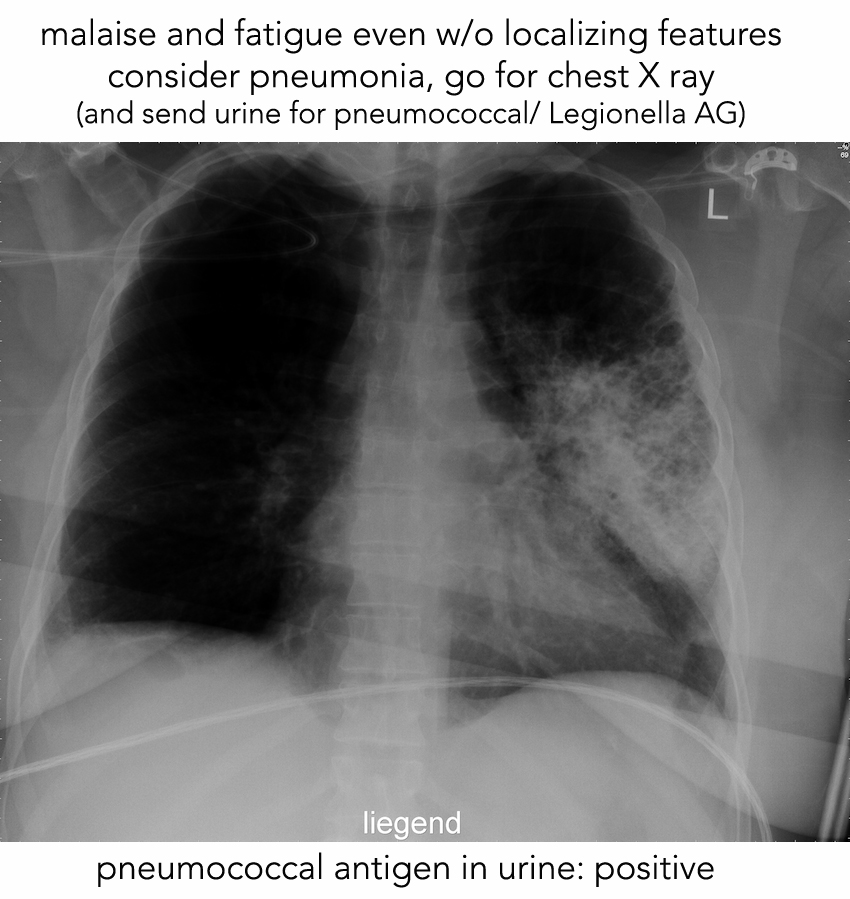

PEARLS pneumonia